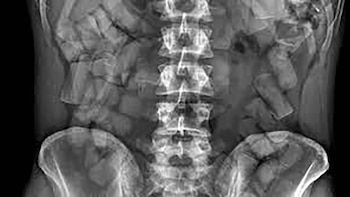

Según el reporte de los investigadores, el equipo médico intentó en primera instancia retirar los estupefacientes a través de las partes íntimas de la mujer. Tras fracasar, procedieron a realizarle una incisión abdominal, lo que causó graves lesiones en venas principales y desencadenó un choque hemorrágico fatal.

La autopsia reveló que la paciente portaba internamente 643 gramos de cocaína y marihuana, evidencia que consolidó la línea investigativa sobre el carácter delictivo del acto.